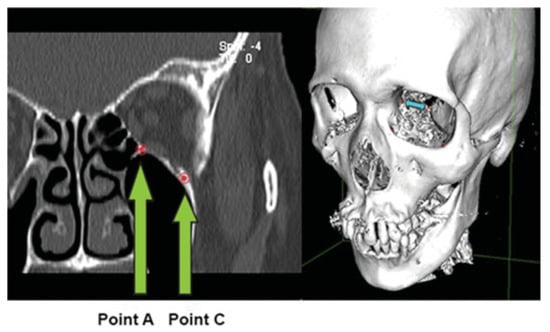

Figure 4.

Limits of the orbital floor posteriorly are bounded medially by the septum between the ethmoid and maxillary sinuses at point A, and laterally by the medial edge of the inferior orbital fissure at point C.

The quantitative aspect of this protocol (Table 2) was modified from a study performed by Schouman et al. []. Using a slice thickness of 2 mm, a total of at least 10 pairs of points of interests were marked in all the coronal images showing the fracture. Three-dimensional (3D) reconstructions of the orbital floor fracture using the 3D Surface Rendering tool are displayed in Figure 7, to illustrate how the surface area of the orbital fracture was obtained. This can also allow the surgeon to visualize the orbital defect and assist in the creation of a personalized preformed orbital implant if surgery is necessary to reconstruct the defect.